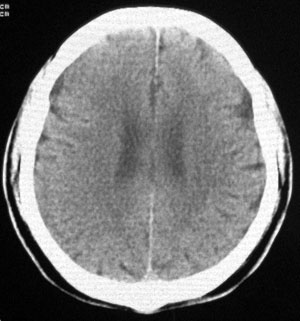

男性,65岁,头疼。 看看这大脑镰,ct值约83hu .

楼主的意思是让我们看大脑镰串珠样钙化,虽然ct值83hu ,也应该是钙化.(循环渐进).

男性,65岁,头疼。 看看这大脑镰,ct值约83hu .考虑蛛血,应该结合临床

感觉应该是生理性钙化

是生理性钙化

头痛与大脑镰钙化应该关系不大。

没有问题的!老年人!头痛的原因很多!大脑镰的钙化这样年龄的病人可以不提示!

大脑镰钙化,应该没有疑问吧